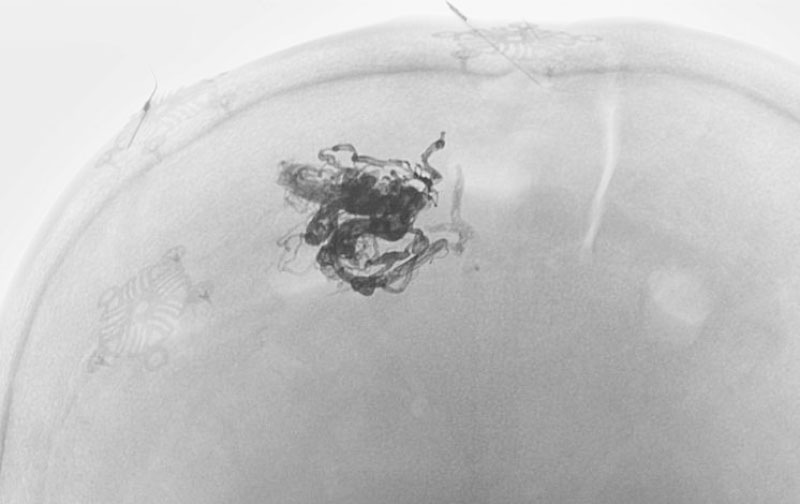

1585

'25年10月6日

脳動静脈奇形

50代

大阪府の病院

中

治療